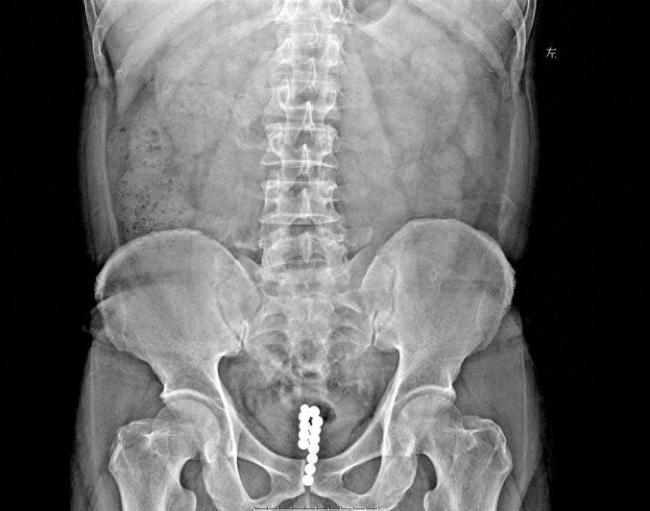

腹部平片检查显示,由于钢珠带有磁性,已经连成一串,滞留在后尿道和膀胱。泌尿外科团队决定为大叔进行经尿道膀胱镜微创手术。手术经历大约半小时,成功取出所有钢珠。术后发现这些钢珠共有13颗,大小不一,最大的直径达1厘米。由于是微创手术且就医及时,大叔恢复较快,现已出院回家休息。